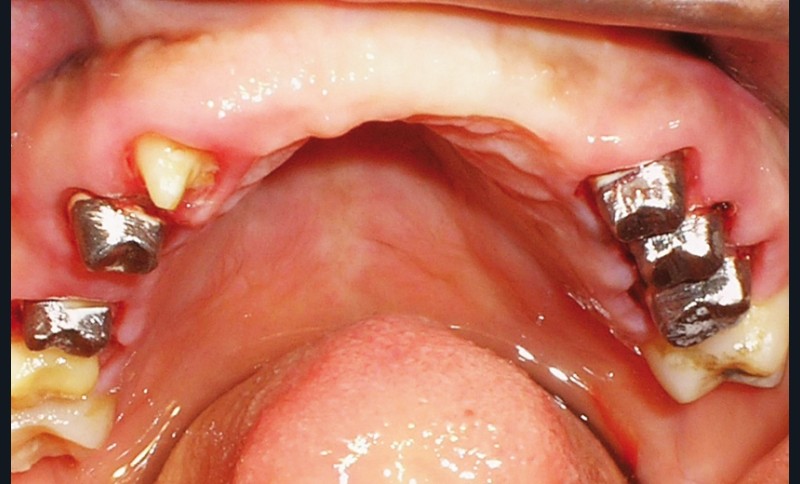

La patiente a été porteuse d’un bridge céramo-métallique de onze éléments au maxillaire pendant huit mois (fig. 1, 2), puis d’un bridge transitoire au maxillaire (fig. 3). Elle signale quelques rares épisodes de saignement probablement dus à l’irritation par la prothèse. Cette dernière se descelle couramment, créant ainsi un préjudice fonctionnel, esthétique et psychologique.

L’examen dentaire ne montre pas de mobilité dentaire. À l’arcade maxillaire, les dents 11, 14, 21, 22, 23 sont absentes. Les dents 13, 15, 24, 25 sont à l’état de racine (fig. 4). Nous notons des reconstitutions coronaires à l’amalgame sur les 26 et 16. À l’arcade mandibulaire, les dents 37, 36, 46, 47 sont absentes et une obturation coronaire à l’amalgame sur 38 est en place. Les bords libres du groupe incisivo-canin et les cuspides des prémolaires sont légèrement abrasés (fig. 5).